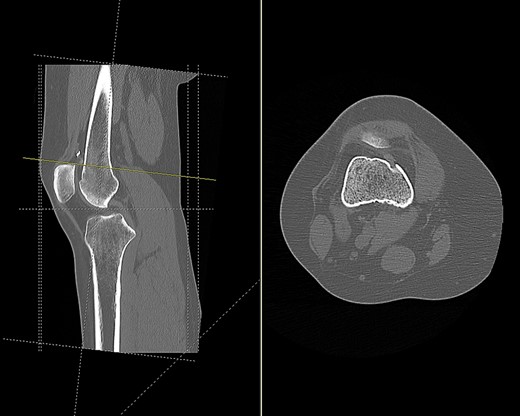

CT (Fig. 1) and MR imaging showed an endobutton and endocord sitting superior to the patella, with both impinging upon the articular surface of the medial patella facet. A metal susceptibility artefact was seen at the medial femoral condyle, which was identified as an interference screw.

CT scan of the right knee showing the endobutton in suprapatellar pouch (sagittal and axial view).